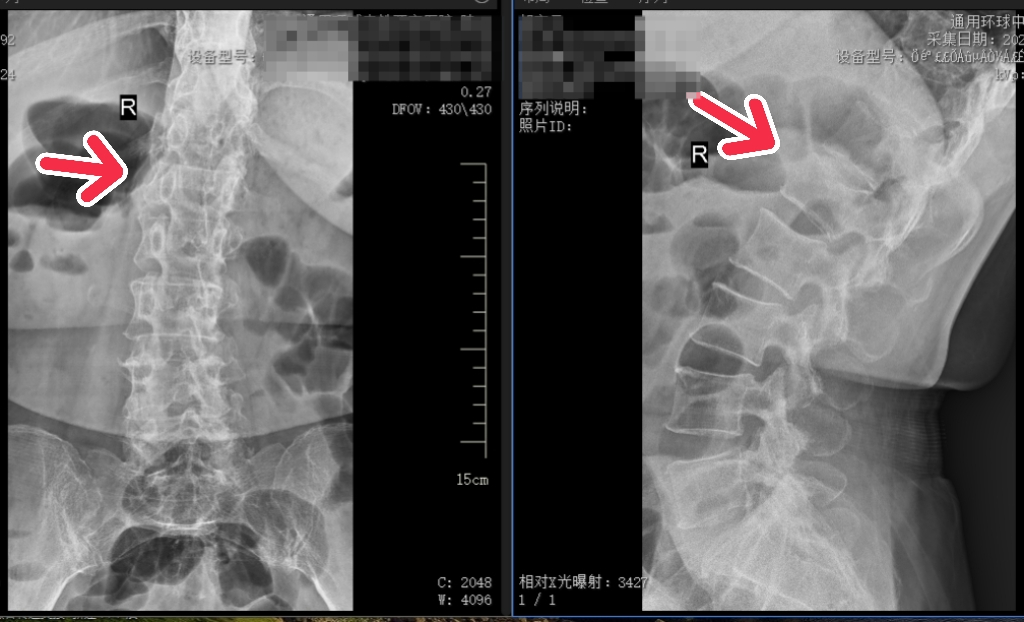

上:术前 / 下:术后

患者血压较高,姬传磊主任团队术前请心血管病院副院长何丽会诊,并制定了周密的手术方案及应急预案。手术团队凭借丰富的经验和娴熟的技术,为患者成功实施了腰1椎体压缩性骨折椎体成形术。

在医护团队的悉心照料下,患者术后次日便可佩戴腰围坐立和下床活动,腰背部疼痛显著缓解,患者及家属对手术效果表示满意,并对姬传磊主任及全体医护人员的精湛医术和贴心服务表达了诚挚谢意。